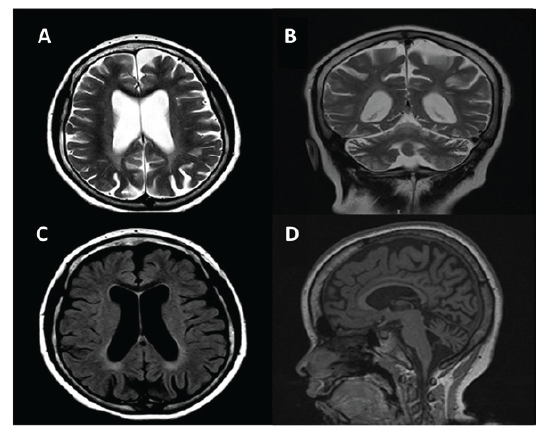

A los nueve años de edad, la paciente refirió disminución progresiva de la agudeza visual y la madre apreció que se tropezaba con los objetos. Se remitió a oftalmología y se identificó alteración retiniana con posible atrofia óptica bilateral. Se tomó una segunda RMN cerebral, documentando atrofia difusa cerebral y cerebelosa, así como hiperintensidades en la sustancia blanca por trastorno de la mielinización retardada (figura 2).

Imágenes de resonancia magnética cerebral (A y B: secuencia de T2 en plano axial y coronal, C: secuencia de FLAIR en plano axial y D: secuencia de T1 en plano sagital) que muestran hallazgos atróficos difusos cerebrales y cerebelosos, así como hiperintensidades en la sustancia blanca por trastorno de la mielinización retardada

Figura 2: Imágenes de resonancia magnética cerebral (A y B: secuencia de T2 en plano axial y coronal, C: secuencia de FLAIR en plano axial y D: secuencia de T1 en plano sagital) que muestran hallazgos atróficos difusos cerebrales y cerebelosos, así como hiperintensidades en la sustancia blanca por trastorno de la mielinización retardada

Fuente: historia clínica de la paciente con autorización.